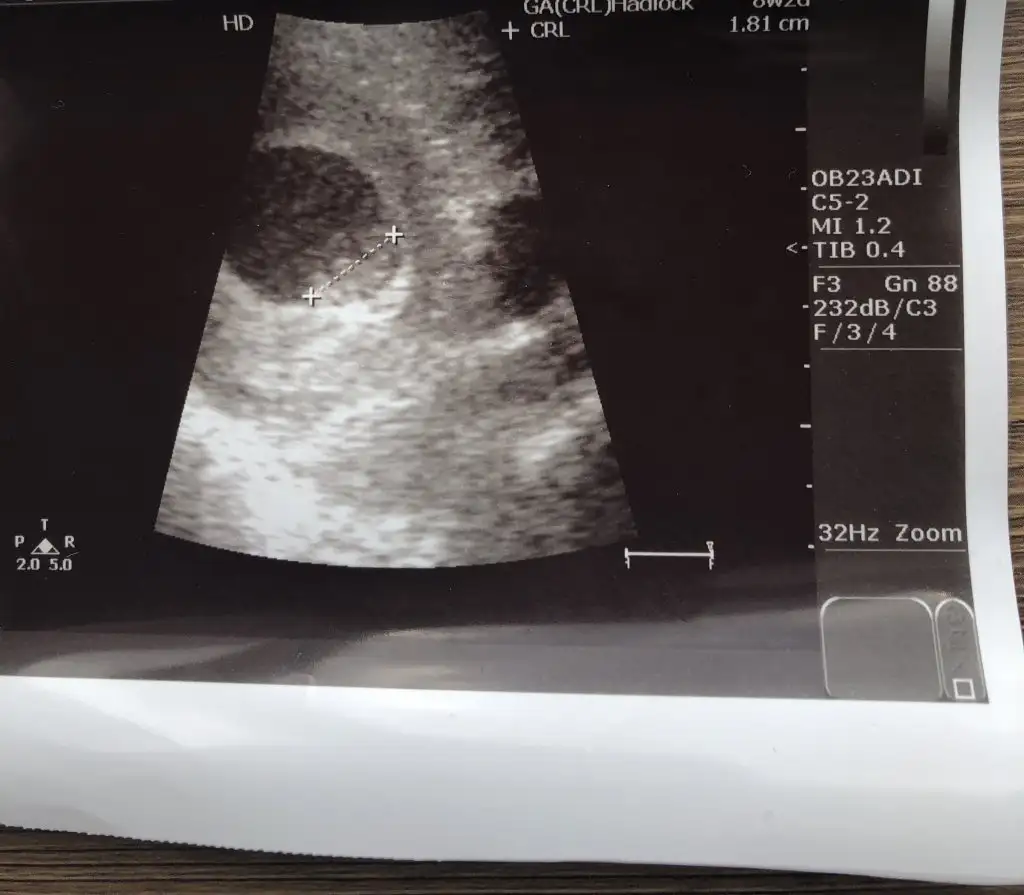

8+3 geç bu teori için yolk saç ne tarafta oluştuysa ona göre yorum yapmak lazım 6 veya 7 haftalık olmalıIkra meyra canım lütfen o güzel tahminlerinden bana da yapar mısın☺ 8+3 günlük karından usg

8+3 geç bu teori için yolk saç ne tarafta oluştuysa ona göre yorum yapmak lazım 6 veya 7 haftalık olmalı